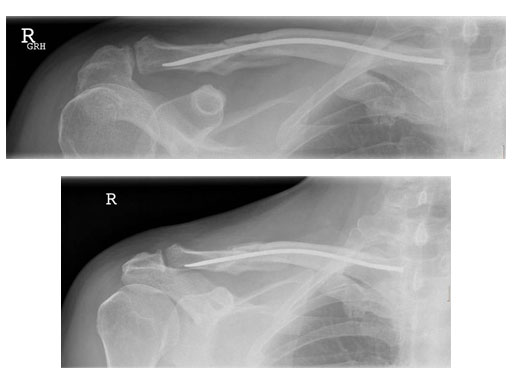

Case 2: 51 years, male, hit by tree